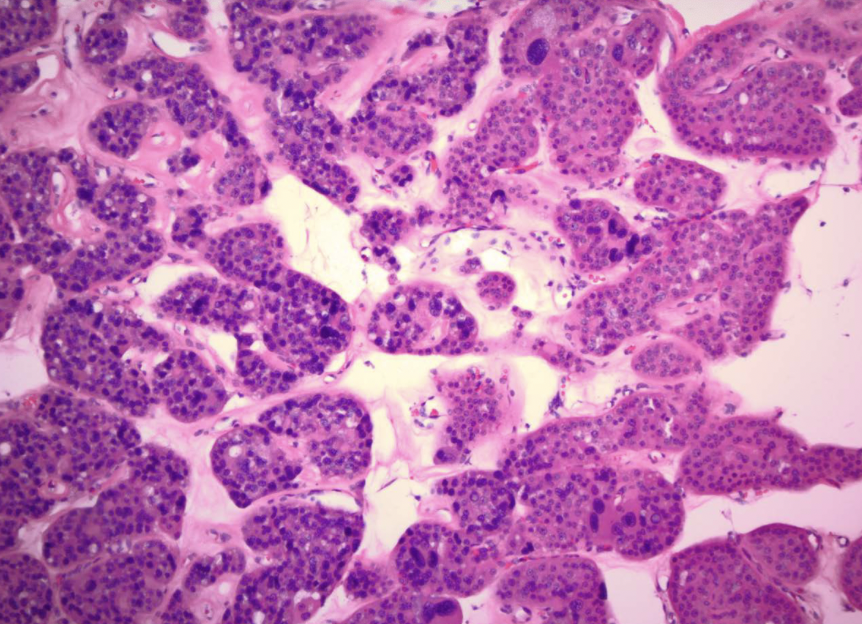

papillary RCC

arise from distal convoluted tubules

multifocal and bilateral

MET

proto-oncogene that encodes the tyrosine kinase receptor for hepatocyte growth factor

papillary RCC

papillary vs. clear cell: multifocal

papillary vs. clear cell: arise in distal tubular epithelium

papillary RCC

papillary RCC

papillary RCC

RCC type: +7 (met), +17, -Y